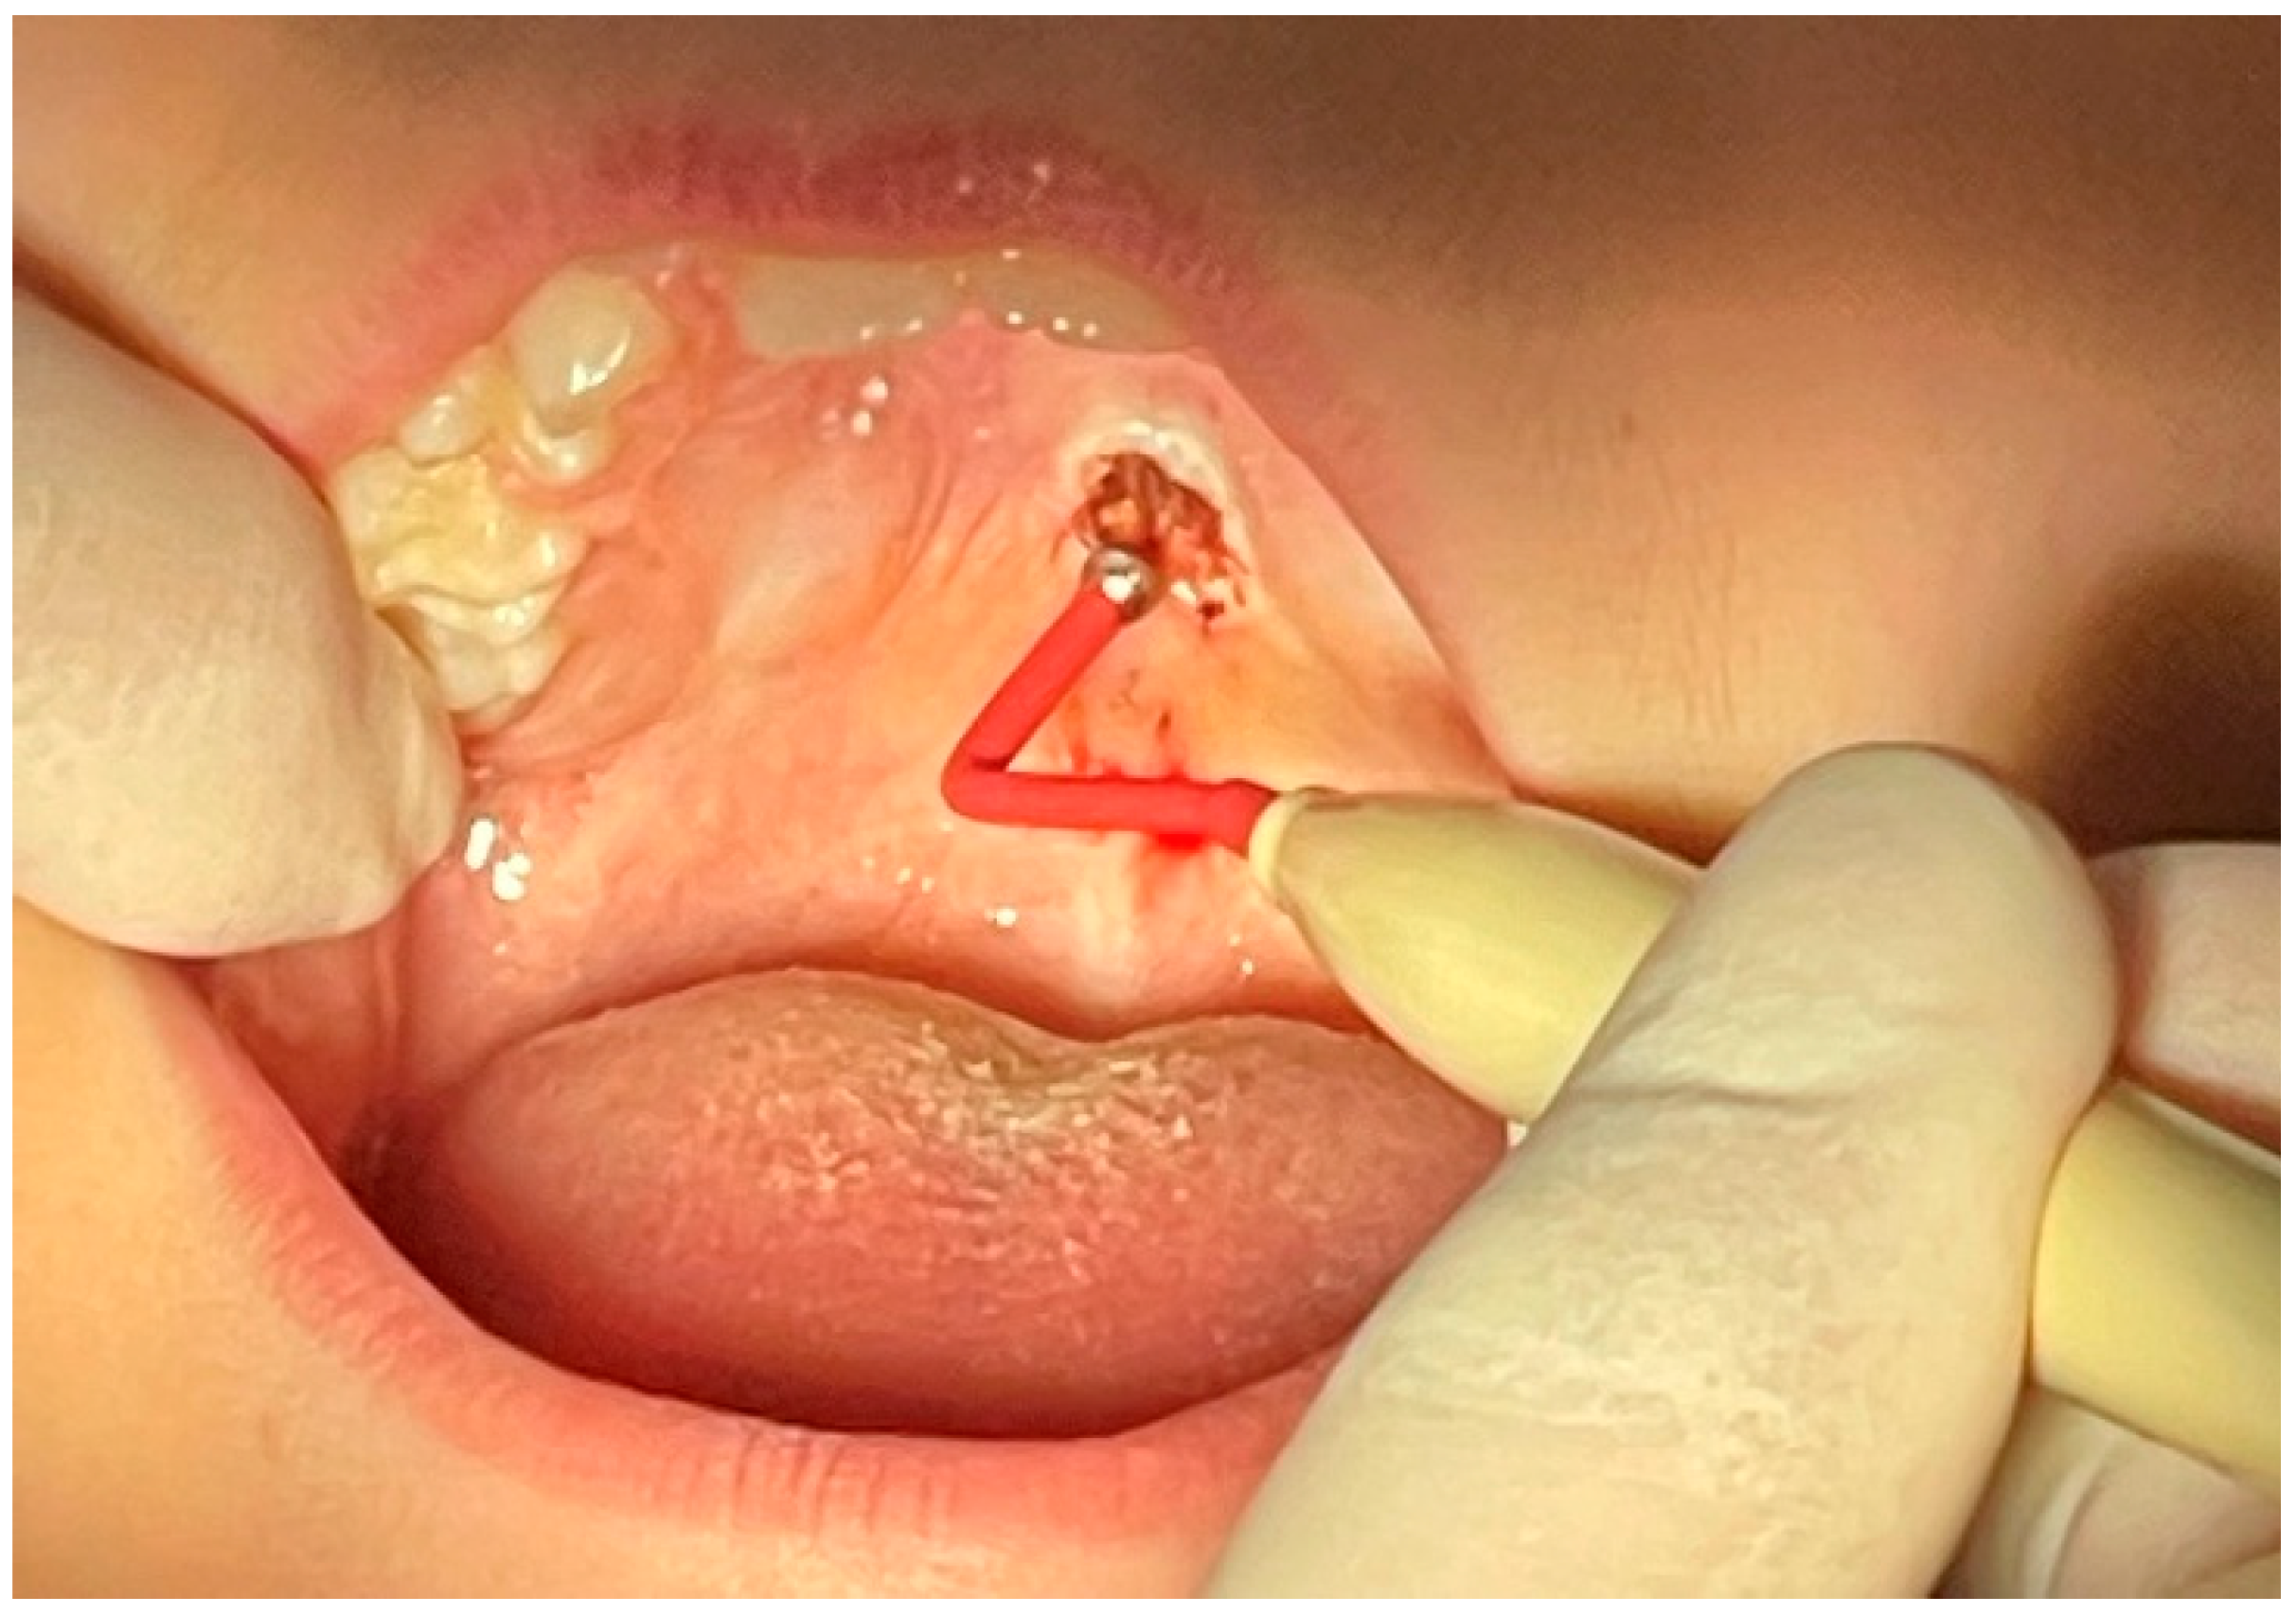

2. Case Presentation